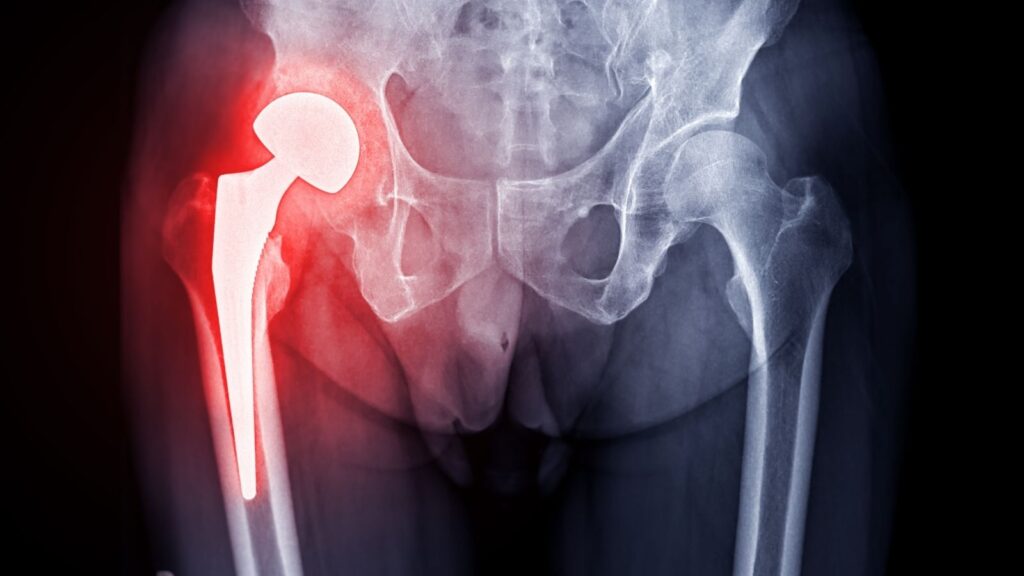

Kalça protezi, kalça eklemini oluşturan kemik yüzeylerin ve kıkırdak dokunun aşınarak görevini kaybettiği durumlarda, hasarlı dokuların cerrahi olarak çıkarılıp yerine metal, seramik ve özel polietilen gibi yüksek dayanıklılığa sahip materyallerden üretilen yapay eklem parçalarının yerleştirilmesi işlemidir. Kalça protezi ile amaç, ağrıya neden olan sürtünmeyi ortadan kaldırmak, hareket sırasında oluşan kısıtlılığı azaltmak ve kişinin günlük hayatına daha bağımsız şekilde dönebilmesini sağlamaktır.

Kalça protezi ameliyatı, hasarlı eklem yüzeyinin çıkarılıp yerine yapay eklemin yerleştirildiği bir cerrahi işlemdir ve ameliyatın temel hedefi, protezin kalça eklemine en doğru açıyla, en doğru dengeyle ve en stabil şekilde yerleştirilmesidir; çünkü protezin doğru yerleştirilmesi hem hastanın ameliyat sonrası yürüme kalitesini artırır hem de protezin uzun ömürlü olmasını sağlar. Ameliyat genel anestezi veya bazı hastalarda spinal anestezi altında yapılabilir ve operasyon süresi genellikle 60–120 dakika arasında değişebilir.

Ameliyatta hangi parçalar takılır?

Kalça protezinin ana parçaları

Uyluk kemiğine yerleştirilen femoral stem

Kalça eklem başını oluşturan protez başı (metal veya seramik)

Leğen kemiğine yerleştirilen asetabular kap

Sürtünmeyi azaltan liner (ara parça)